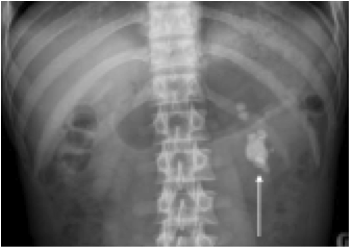

What can you see in this abdominal X-ray?

Staghorn calculus in left kidney.